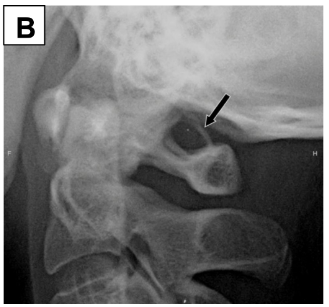

Se presentan dos pacientes, un varón de 35 años (A) y una mujer de 32 años (B), con cervicalgia crónica. En la radiografía lateral de columna cervical se encontró un puente óseo sobre el agujero de la arteria vertebral C1, característico de pontículus posticus. Se postula que el pontículus posticus surge de la osificación del segmento lateral del ligamento atlanto occipital superior, siendo unilateral o bilateral. Puede ser un hallazgo imagenológico incidental en un paciente asintomático; sin embargo, puede provocar isquemia vertebro-basilar, vértigo, cervicalgia y cefalea. Entre los hallazgos, en la radiografía lateral de cuello se evidencia una calcificación parcial o completa sobre el techo óseo del agujero de la arteria vertebral C1, tal como se encontró en ambos casos, por lo que es importante tener en cuenta este hallazgo e informarlo en pacientes que cursen con algunos de los síntomas descritos.

We present two patients, 35-year-old male (A) and 32-year-old woman (B), with chronic cervicalgia. On whose lateral radiograph of the cervical spine demonstrates an osseous roof over the C1 vertebral artery foramen, characteristic of ponticulus posticus. Ponticulus posticus arises from ossification of the lateral segment of posterior atlantooccipital ligament, being unilateral or bilateral. It may be an incidental imaging finding in an asymptomatic patient; however, it can cause vertebrobasilar ischemia, vertigo, neck pain and headache. The lateral neck x-ray usually shows a partial or complete osseous roof over C1 vertebral artery foramen, as shown as in both cases, so it is important to take this finding into account and report it in patients with some of the symptoms described.